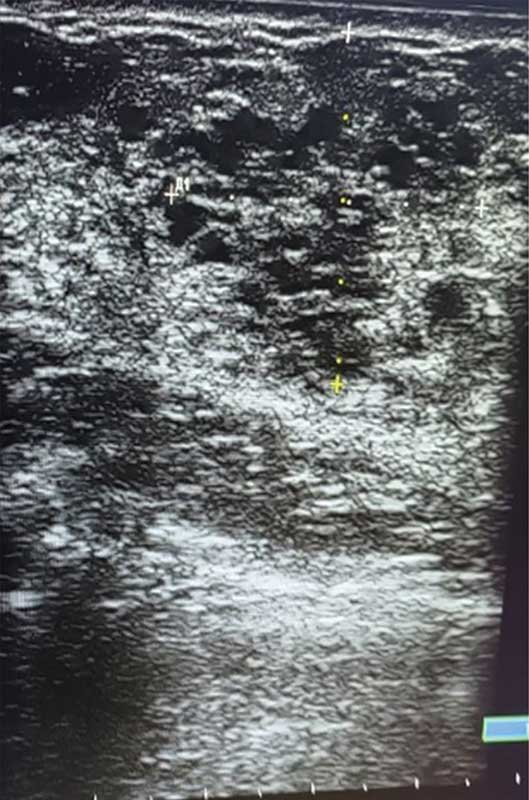

Рис. 3. Ювенильная фиброаденома правой молочной железы у 15-летней девочки

Опухоли подразделяют на доброкачественные и злокачественные [1, 5]. У девочек наиболее распространена ювенильная фиброаденома – доброкачественная фиброэпителиальная опухоль, обычно возникающая в пубертате и склонная к быстрому росту (рис. 2) [5, 11, 12]. Чаще это одиночный узел. Множественные очаги отмечают примерно у каждой пятой пациентки, двусторонние – примерно у каждой десятой [5, 12, 13].

На УЗ-картине солидное, гипоэхогенное по сравнению с тканью МЖ образование однородной структуры, с четкими контурами. Нередко наблюдается дорсальное псевдоусиление без акустической тени (рис. 3–5) [5, 7, 10].